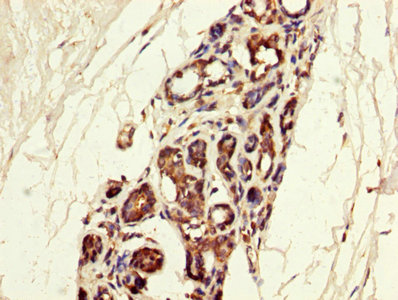

IHC (Immunohiostchemistry)

(IHC image of AAA114181 diluted at 1:300 and staining in paraffin-embedded human breast cancer performed on a Leica Bond system. After dewaxing and hydration, antigen retrieval was mediated by high pressure in a citrate buffer (pH 6.0). Section was blocked with 10% normal goat serum 30min at RT. Then primary antibody (1% BSA) was incubated at 4 degree C overnight. The primary is detected by a biotinylated secondary antibody and visualized using an HRP conjugated SP system.)